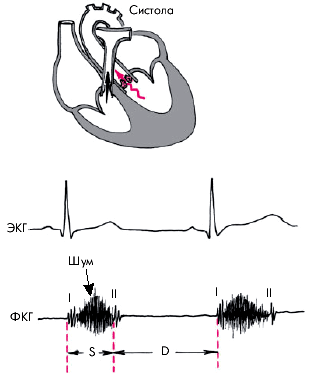

В типичных случаях для стеноза устья аорты характерен грубый интенсивный систолический шум в зоне аускультации аорты и разнообразные изменения II и I тонов, чаще их ослабление (рис. 8.47).

| Рис. 8,47. Изменения ФКГ при стенозе устья аорты (второе межреберье справа): ослабление I и II тонов, высокоамплитудный систолический шум ромбовидного характера, занимающий всю систолу. S - систола, D - диастола. Вверху показан основной механизм возникновения шума (турбулентный ток крови) |